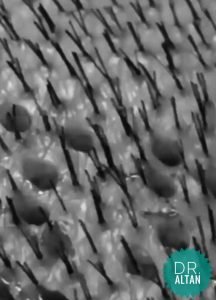

How does it looks beforehair transplant

On the day of the hair transplant , the hairs are completely shortened to facilitate the removal of the hair follicles.